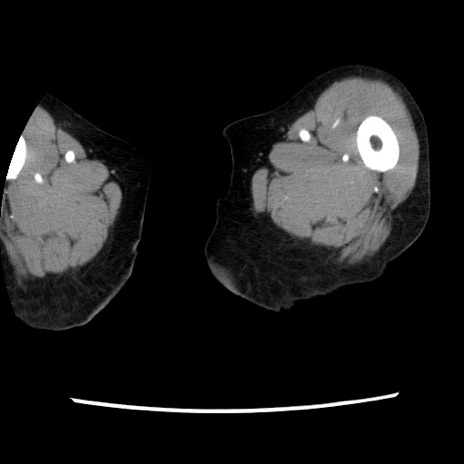

【症例】80歳代女性

【主訴】腹痛

【現病歴】8時間前から腹痛あり来院。

【既往歴】糖尿病、脂質異常症、子宮体癌にて子宮全摘術

【身体所見】意識清明・会話良好だが腹痛で苦悶様、全腹部にわたって反跳痛と圧痛あり

【データ】WBC 13600、CRP 0.14、LDH 224、CK 90